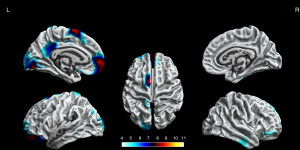

Cortical gyrification

The BECTS patients showed significantly increased cortical gyrification in the left hemisphere and partial right hemisphere, including superior frontal gyrus, frontal pole, lingual gyrus, lateral occipital gyrus, isthmus cingulate gyrus, posterior cingulate gyrus, postcentral gyrus, inferior parietal gyrus, supramarginal gyrus, and pars opercularis gyrus in the left hemisphere, inferior temporal gyrus, middle temporal gyrus, pars orbitalis gyrus, superior frontal gyrus in the right hemisphere (P<0.05, FWE corrected, Figure 2). The decreased cortical gyrification was only in the left hemisphere, including the insula, pars triangularis gyrus, pars opercularis gyrus, inferior temporal gyrus, lateral occipital gyrus, superior temporal gyrus, middle temporal gyrus and precentral gyrus (P<0.05, FWE corrected, Figure 3).